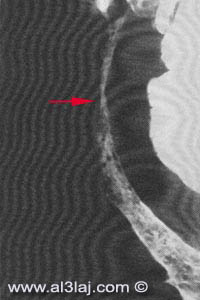

في المنظر المرفق المقابل صورة لأشعة وجبة باريوم تبين

الضيق (السهم) الذي يحصل في نهاية الأمعاء الدقيقة نتيجة للإصابة

بمرض كرون.